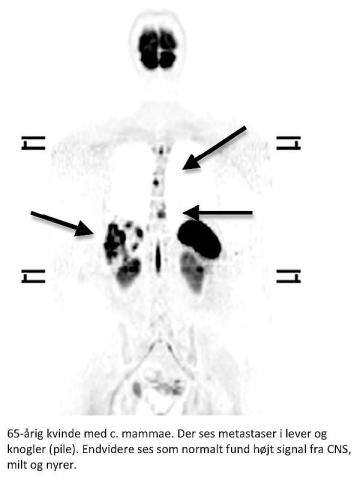

Helkropsskanning med DWI blev beskrevet i 2004 [2]. Undertrykkelse af baggrundssignalet gør, at bl.a. maligne læsioner fremstår som sorte områder som kendt fra PET/CT (se figuren).